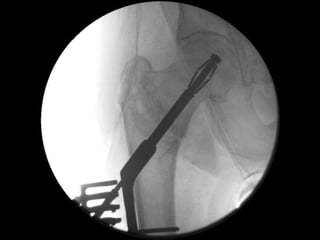

‘Tip-Apex’ distance

Tip-Apex Distance (combined >25mm) is a major factor in predicting cut-out

Baumgaertner et al. JBJS Am 1995; 77:1058-64

‘Tip-Apex’ fixation maintained